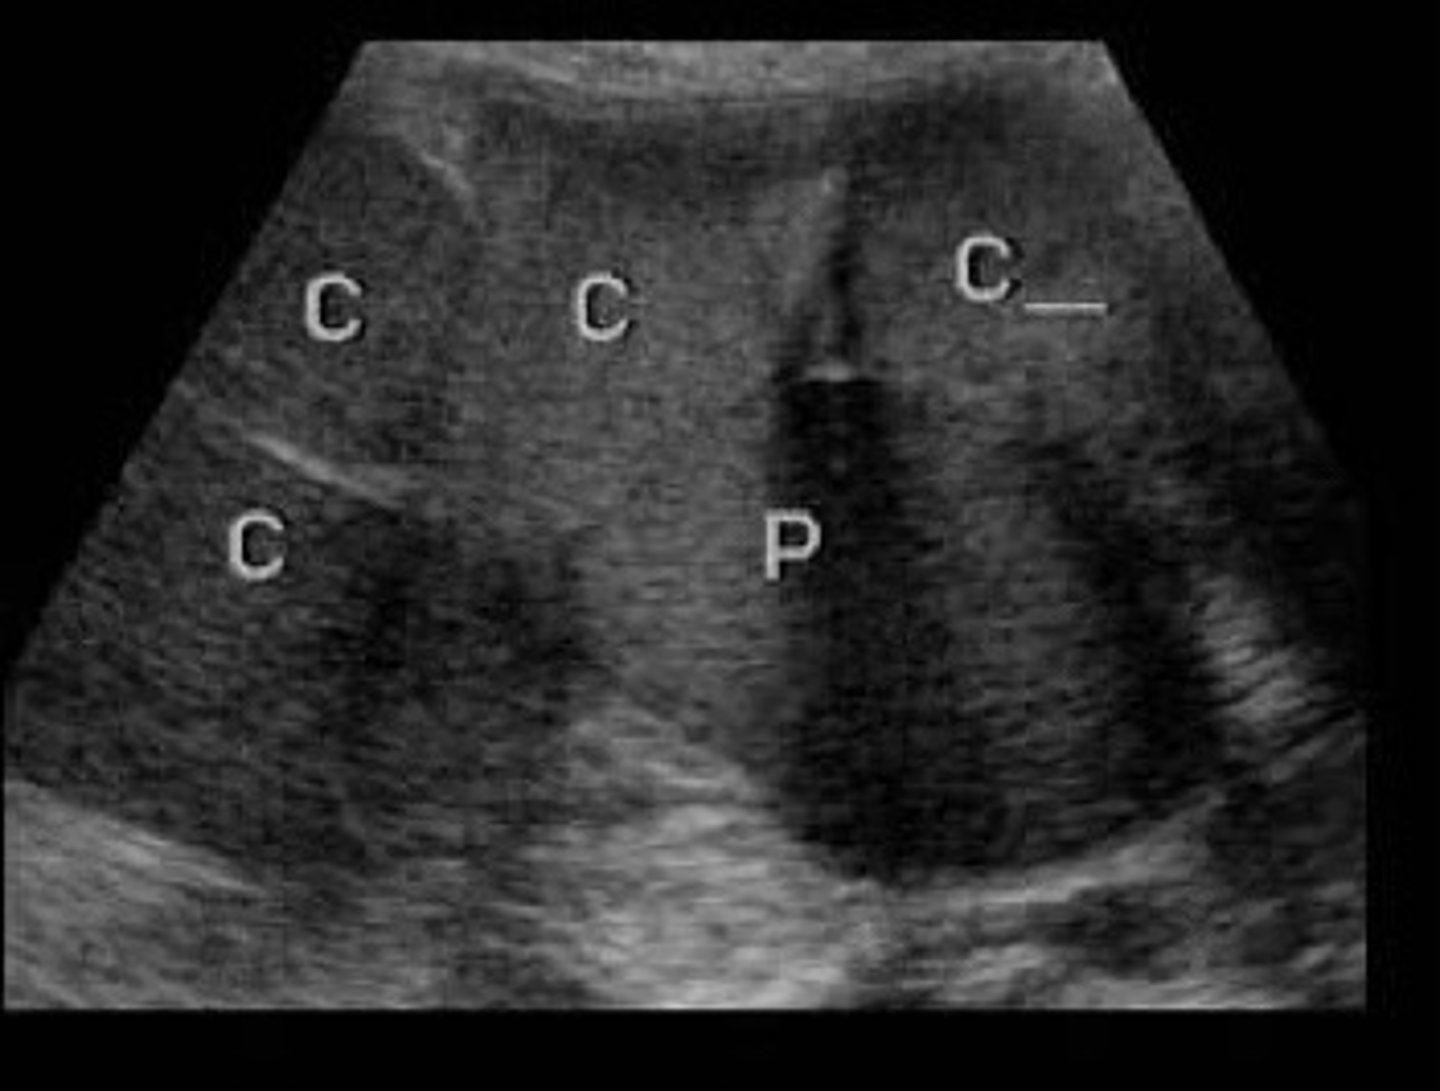

Cortical thinning, extensive enlargement of renal sinus and calyces, loss of individual calyx definition

Describe the appearance of grade 3 hydro

How collecting system is blown out and very dilated that it starts pushing on the cortex bc not enough room in the kidney

Why do we see cortical thinning with grade 3 hydro

Loss of the clubbed shape of the calyces, they start to loose their normal shape because so dilated

Describe the appearance of the calyces in grade 3 hydro

Grade 3 hydro

What does this image show